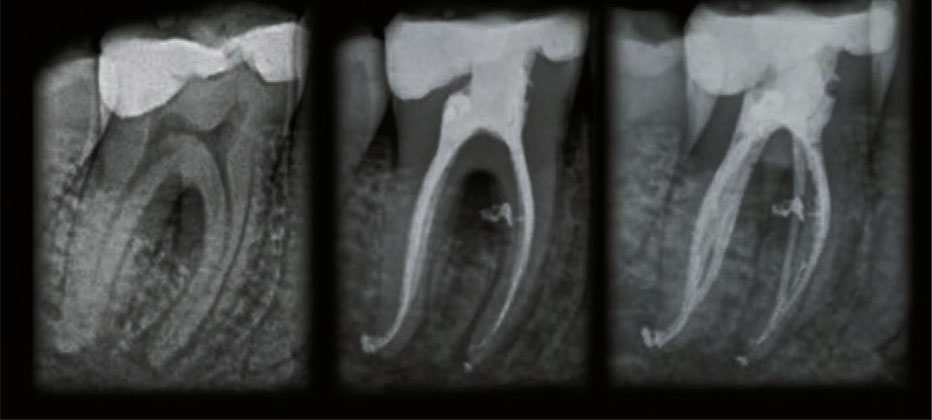

ЭНДОДОНТИЯ

— Waterlase обеспечивает предсказуемую и эффективную дезинфекцию, при этом сводит к минимуму дискомфорт после лечения и позволяет максимально сохранить ткани зуба.